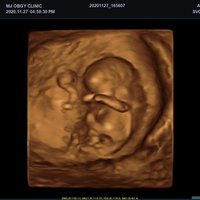

Mit dem X-CUBE 90 beginnt ALPINION eine neue Generation an Farbdopplersystemen, die X- CUBE Serie. Mit Bildverarbeitungstechnologien eines Premiumsystems und neuen Breitband- Schallköpfen mit X + Crystal Signature™ Technologie wartet das neue X-CUBE 90 auf.

Neben der hohen Bildqualität liegt ein weiterer Fokus auf der Vereinfachung und der Anpassung der Bedienung des Ultraschallgeräts. Individuell programmierbare Workflows und ein erweitertes Spektrum an automatisierten Messungen ermöglichen ein schnelleres und genaueres Arbeiten in jeder Situation.

X + Architecture

Die X + Architecture ist eine erstklassige Imaging-Plattform, die durch die Kombination von X + Crystal Signature™, der Schallkopftechnologie mit hoher Sensitivität und Breitbandigkeit, und X + FIT, ALPINIONs modernste Beamforming- und Datenverarbeitungstechnologiengeschaffen wurde. X + FIT ist eine neue Technologie, die den Schallstrahl scharf fokussiert sendet, ein großes Datenvolumen empfängt und mit hoher Geschwindigkeit verarbeitet. Darüber hinaus nutzt X + Crystal Signature™ Einkristalle und unser eigenes entwickeltes Schallkopfmaterial, um eine hervorragende Brillanz zu erzielen und die Diagnosemöglichkeiten zu erweitern.